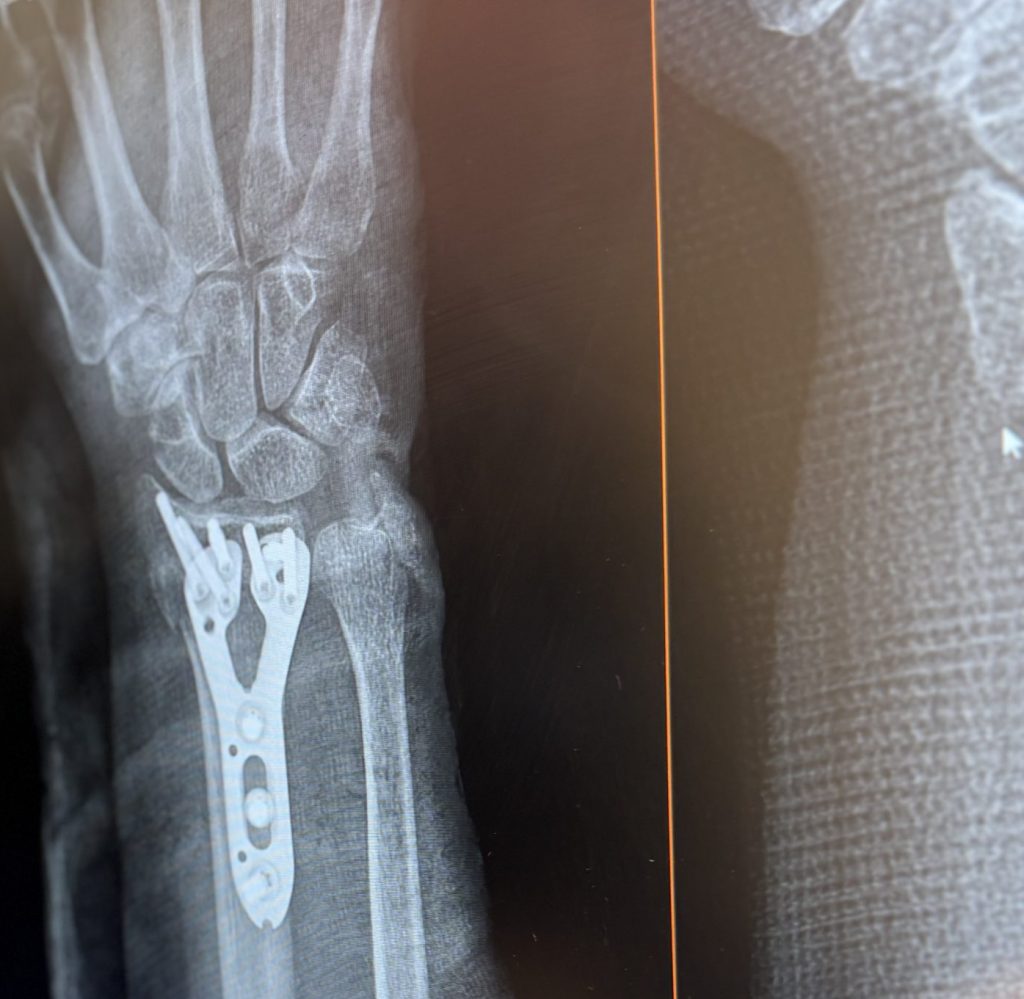

Distal Radius Fracture: Diagnosis, Treatment and Recovery

Just a few months ago, I saw Dr. Matthew Abola for a second opinion on wrist surgery. Dr. Abola, a fairly new hand specialist, is a compassionate professional who gained my trust with his open knowledge and calm, balanced demeanor. With updated x-rays and a supplemental CT scan, Dr. Abola was able to assure me with confidence that I would be able to heal on my own satisfactorily and without surgery. Alexandra then fitted me with a custom, lightweight cast before sending me on my way, thanks to a seamless visit managed by Jessica. Three weeks later, I was happy to attend my follow ups with Dr. Abola and his team at the new and convenient Paramus location at Midland Avenue, where I continue to receive quality occupational therapy with Taylor. Thank you, Dr. Abola and team, for getting me back on the tennis and pickleball courts!